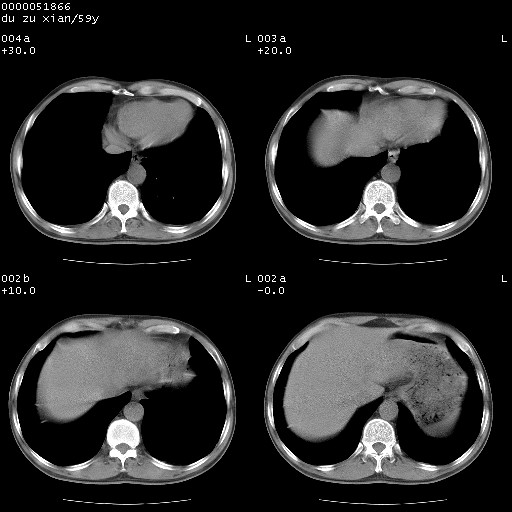

以下是引用宇宙ct在2008-8-25 23:21:00的发言:[br]右肺周围性肺癌并肋骨转移,纵隔淋巴结转移。

以下是引用zsl6918在2008-8-25 22:40:00的发言:[br]右肺周围性肺癌并肋骨转移,纵隔淋巴结转移。

以下是引用zy_zj在2008-8-26 15:24:00的发言:[br]单从病变本身,我倾向良性炎性病变,但肋骨转移了,所以说是考虑右肺周围性肺癌并肋骨、纵隔淋巴结转移可能性大。